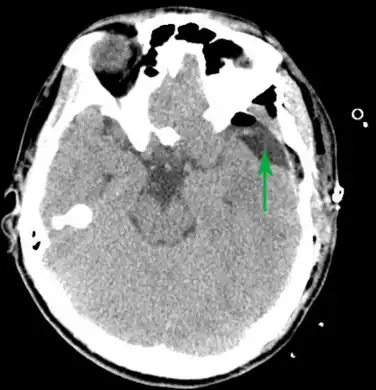

-

Male with complicated arachnoid cyst -

Arachnoid cyst as seen on a CT image of the brain -

Axial CT showing a typical arachnoid cyst left temporal

Diagnosis is principally by MRI. Frequently, arachnoid cysts are incidental findings on MRI scans performed for other clinical reasons. In practice, diagnosis of symptomatic arachnoid cysts requires symptoms to be present, and many with the disorder never develop symptoms.